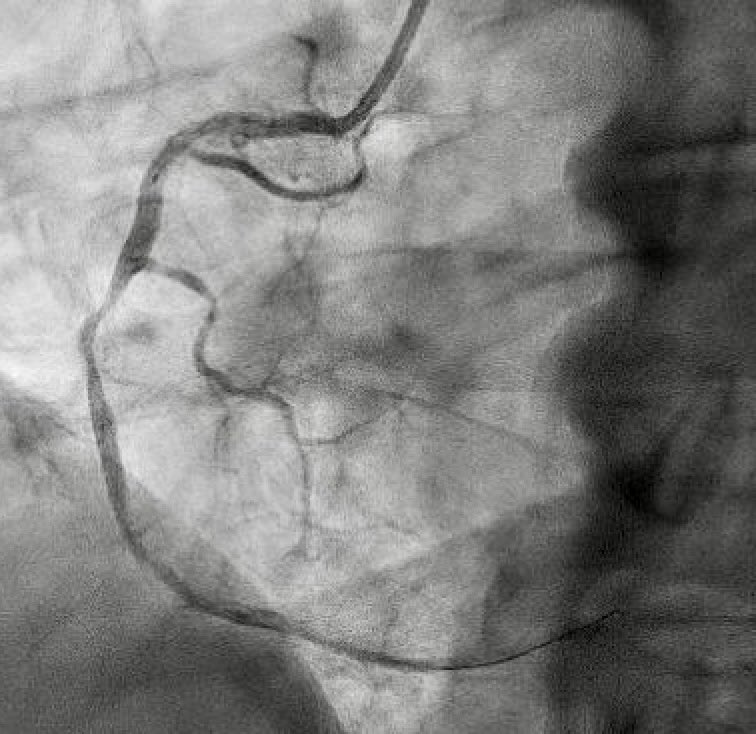

2/2 large RCA-RA /CS fistula. AO 90/63 PA 53/15. O2% RA 61 PA 65 AO 96. How do you explain RA sat( I expected 80s) and normal RV size? @ramymandoMD @IvanHansonMD @amrabbasmd @BeaumontIC @BeaumontCards @Babar_Basir @CMichaelGibson @NalassaadNihad @ANbilolikar

@amin_mulji @ramymandoMD @IvanHansonMD @amrabbasmd @BeaumontIC @BeaumontCards @Babar_Basir @CMichaelGibson @NalassaadNihad @ANbilolikar @OliviaMAllenDO Moderate LAD stenosis. Medical tx despite the significant “ angiographic “ shunt his R heart data and echo do not suggest clinically significant shunting.

@amrabbasmd @ramymandoMD @IvanHansonMD @BeaumontIC @BeaumontCards @Babar_Basir @CMichaelGibson @NalassaadNihad @ANbilolikar So how do you explain the inferior ST elevation And troponin bump when he was dehydrated with relatively lower blood pressure? Just slower coronary flow in that huge artery ?

@raatassi @ramymandoMD @IvanHansonMD @amrabbasmd @BeaumontIC @BeaumontCards @Babar_Basir @CMichaelGibson @NalassaadNihad @ANbilolikar Planning CTA as OP to better understand. I’m still puzzled by the lack of high RA sat and significant RV dilation with the amount of “ contrast shunt”

@LuaySayed @ramymandoMD @IvanHansonMD @amrabbasmd @BeaumontIC @BeaumontCards @Babar_Basir @CMichaelGibson @NalassaadNihad @ANbilolikar Is it rca - cs- ra?